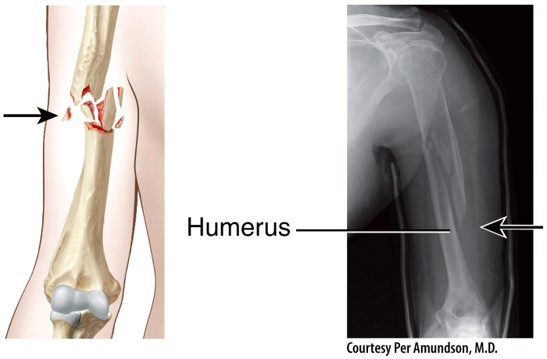

Open (Compound) Bone Fracture

Comminuted Bone Fracture